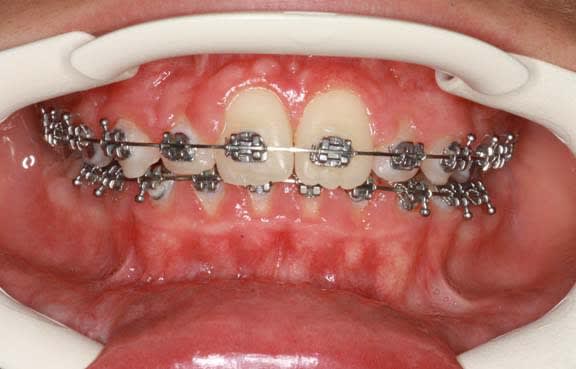

Seule la 11 arrive sur l’arcade

Il faut donc faire une 2° chirurgie et coller un anneau de traction

Je décide faire moi-même, la 2° chirurgie

la 21 est en placement, sans trop de Pbs.

La suite n’est plus qu’une formalité avec les frictions faibles

il a fallu passer beaucoup de temps en explication avec tout le monde, et malgré cela, le manque de motivation de l’enfant s’est traduit par de grosses négligences au brossage